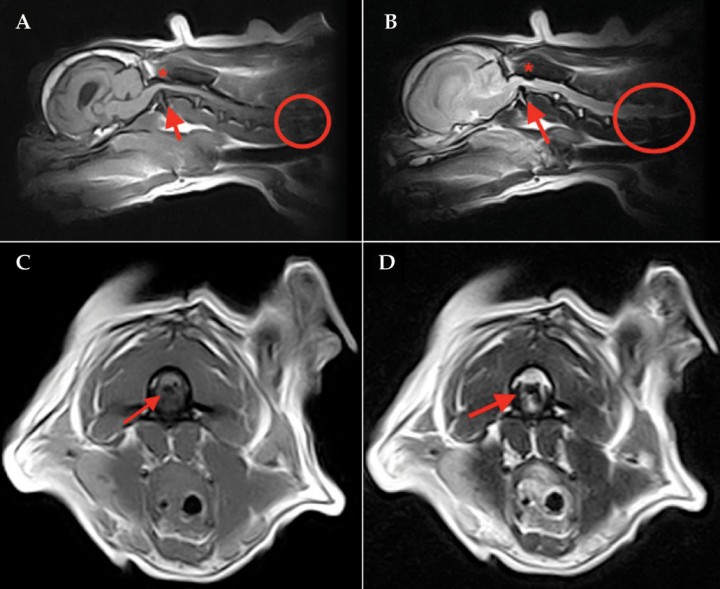

La Mielopatía Degenerativa (DM) es una enfermedad neurodegenerativa y puede estar presente en la raza del Pastor Blanco Suizo. Es una enfermedad que afecta de manera progresiva la degeneración de la médula espinal y por tanto a la movilidad del perro.

Se trata de una enfermedad crónica de evolución gradual que afecta principalmente a perros de edad avanzada, suele empezar a manifestarse hacia los 7 u 8 años de edad, ocasionándoles un progresivo deterioro en las extremidades traseras (con el tiempo estos síntomas se extenderán a las extremidades delanteras), lo cual se traduce en:

* Una falta de coordinación

* Dificultad para caminar

* Dificultad para mantenerse en pie

* Caídas.

Es importante tener en cuenta que la Mielopatía degenerativa no tiene cura, pero la DM es fácilmente detectable mediante un análisis de sangre para prevenir su aparición en futuras generaciones.